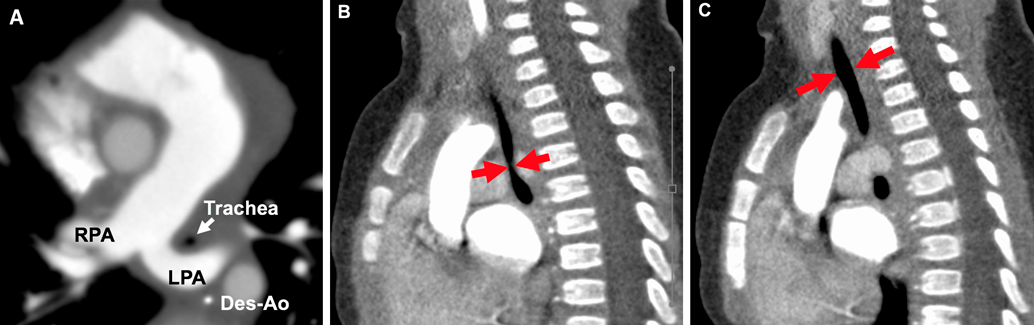

We evaluated the details of tracheal stenosis using CT (Fig. 1A) and calculated the stenotic segment ratio, which was estimated by the following formula (Fig. 1B, 1C)4): Normal tracheal lumen diametertracheal lumen diameter of the most stenotic part Normal tracheal lumen diameter We also calculated the longitudinal stenotic tracheal segment ratio as shown in Fig. 2. Long-segment tracheal stenosis was defined as the ratio of the stenotic tracheal segment to that of the entire tracheal length of >50%.5)

Fig. 2 Reconstructed coronal plane CT image in patient No. 5

The longitudinal stenotic segment ratio was 84% of the entire length.